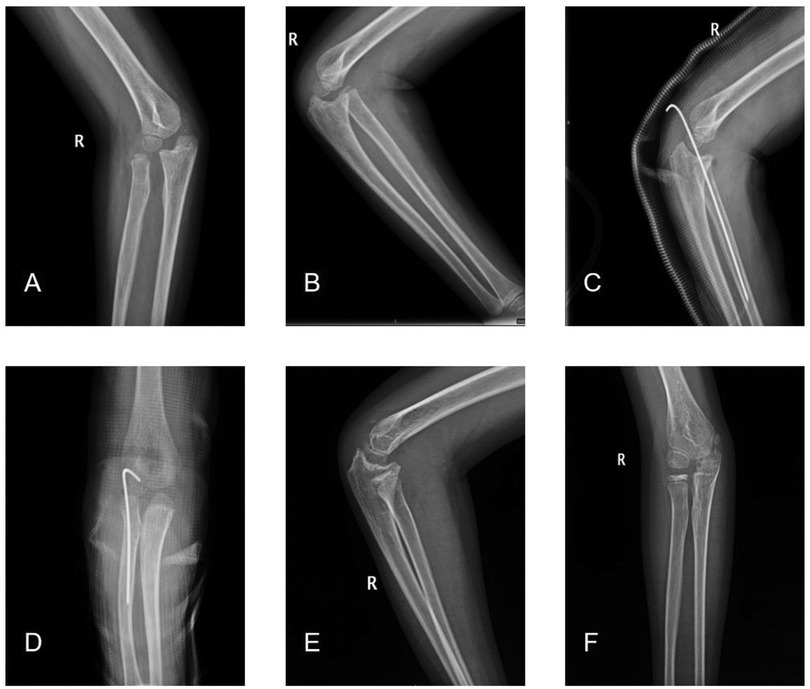

Objective: The aims of this study were to review our cases of missed Monteggia fracture treated by open reduction of the radial head with or without ulnar osteotomy and to investigate the necessity of ulnar osteotomy in surgical treatment of missed Monteggia fracture. Materials and methods: The children were divided into 2 groups according to the surgical methods: patients in group A were treated with Kirschner wire or external fixation after ulnar osteotomy and Kirschner wire fixation after humeroradial joint open reduction. Patients in group B were treated with open reduction of humeroradial joint fixed with Kirschner's wire, and ulna osteotomy was not performed. The imaging results of the most recent postoperative follow-up were evaluated using Nakamura grading criteria, and the elbow function was evaluated using Mayo elbow function score. Results: There were 53 patients in group A and 14 patients in group B. The mean age of children in group A was older than that in group B and the delay time of diagnosis and treatment in group A was longer than that in group B. There was no significant difference in the proportion of excellent postoperative Nakamura score between group A and group B (p>0.05). There was no significant difference in Mayo score of elbow joint after operation between group A and group B (P>0.05). In group A, complications of children were postoperative dislocation of humeroradial joint, broken Kirschner wire of humeroradial joint, occasional mild pain in the elbow joint and the Kirschner wire ends penetrating the subcutaneous tissue which were treated through surgery. In Group B, complications of children were postoperative dislocation of humeroradial joint, broken Kirschner wire of humeroradial joint and myositis ossificans. Conclusion: Ulnar osteotomy is not necessary for all children with missed Monteggia fracture. Open reduction of the humeroradial joint followed by Kirschner wire fixation can be considered as a surgical option for that younger patients with a short duration of delay.